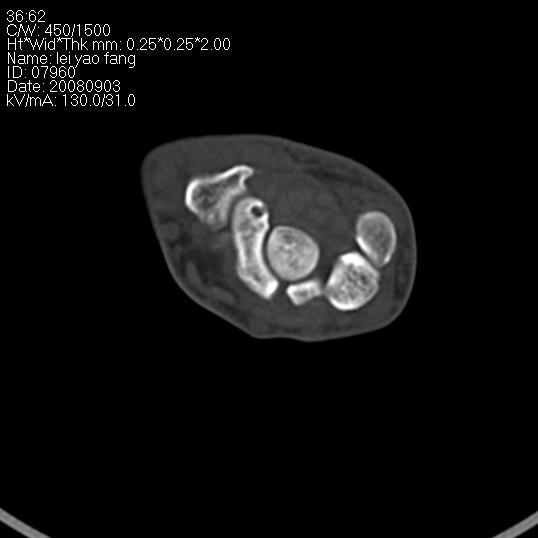

以下是引用杀毒软件在2008-9-4 17:41:00的发言:[br]考虑----舟骨囊肿